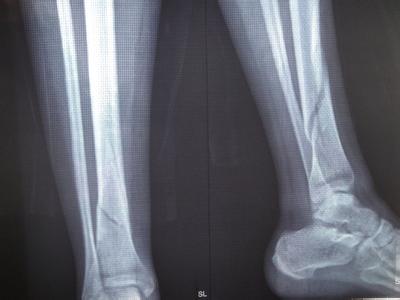

骨折的治疗需要看具体的伤病情况,如果病情较轻,可以采用保守治疗,如果病情较重,就需要进行手术治疗了。下面是关于西医治疗骨折的选择依据。

1、保守治疗

如果骨折移位不明显,或经过手法复位后,可以通过石膏、夹板或持续牵引或等治疗维持骨折端的位置直至骨折愈合,则可以考虑保守治疗;但必需考虑 保守治疗所致并发症的影响。如老年患者髋部骨折,无明显移位,保守治疗需卧床6-12周甚至更长的时间,治疗期间可能会出现坠积性肺炎、泌尿系统感染等并发症,严重时可危及生命。

2、手术治疗

通常为切开复位内固定术。以下情况需考虑切开复位。